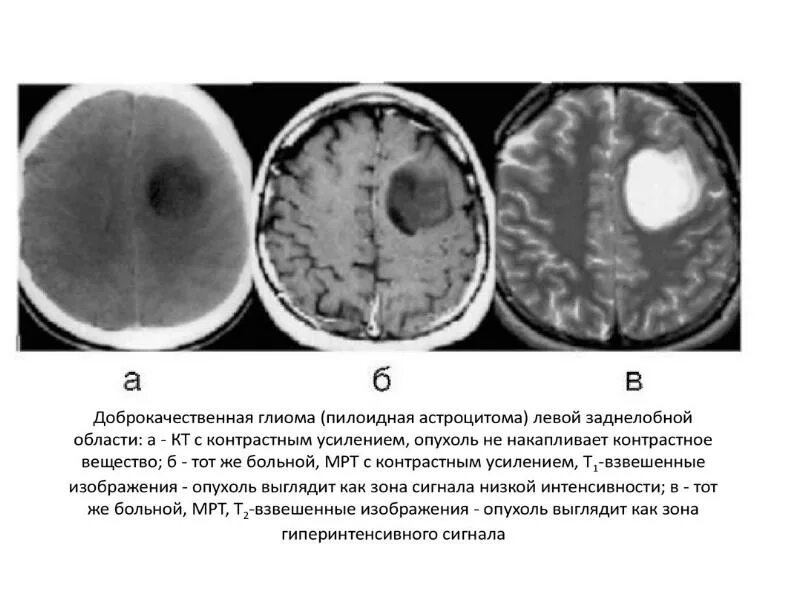

Сколько живут с доброкачественной опухолью головного мозга